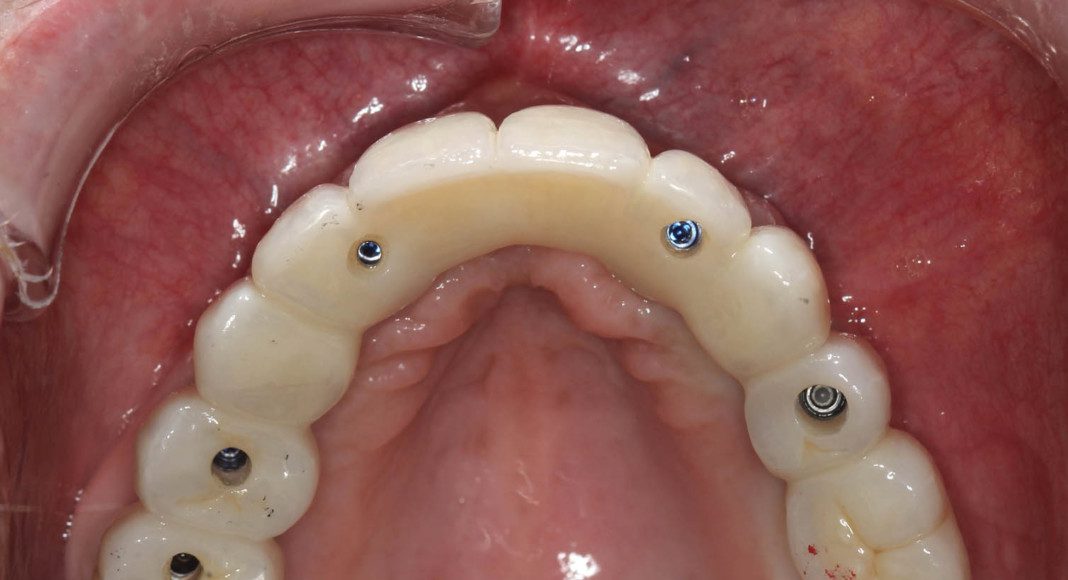

Occlusal view, day of delivery. If you look closely, you can see the final prosthetic screw (blue). This channel is covered with composite resin and patient comfort.